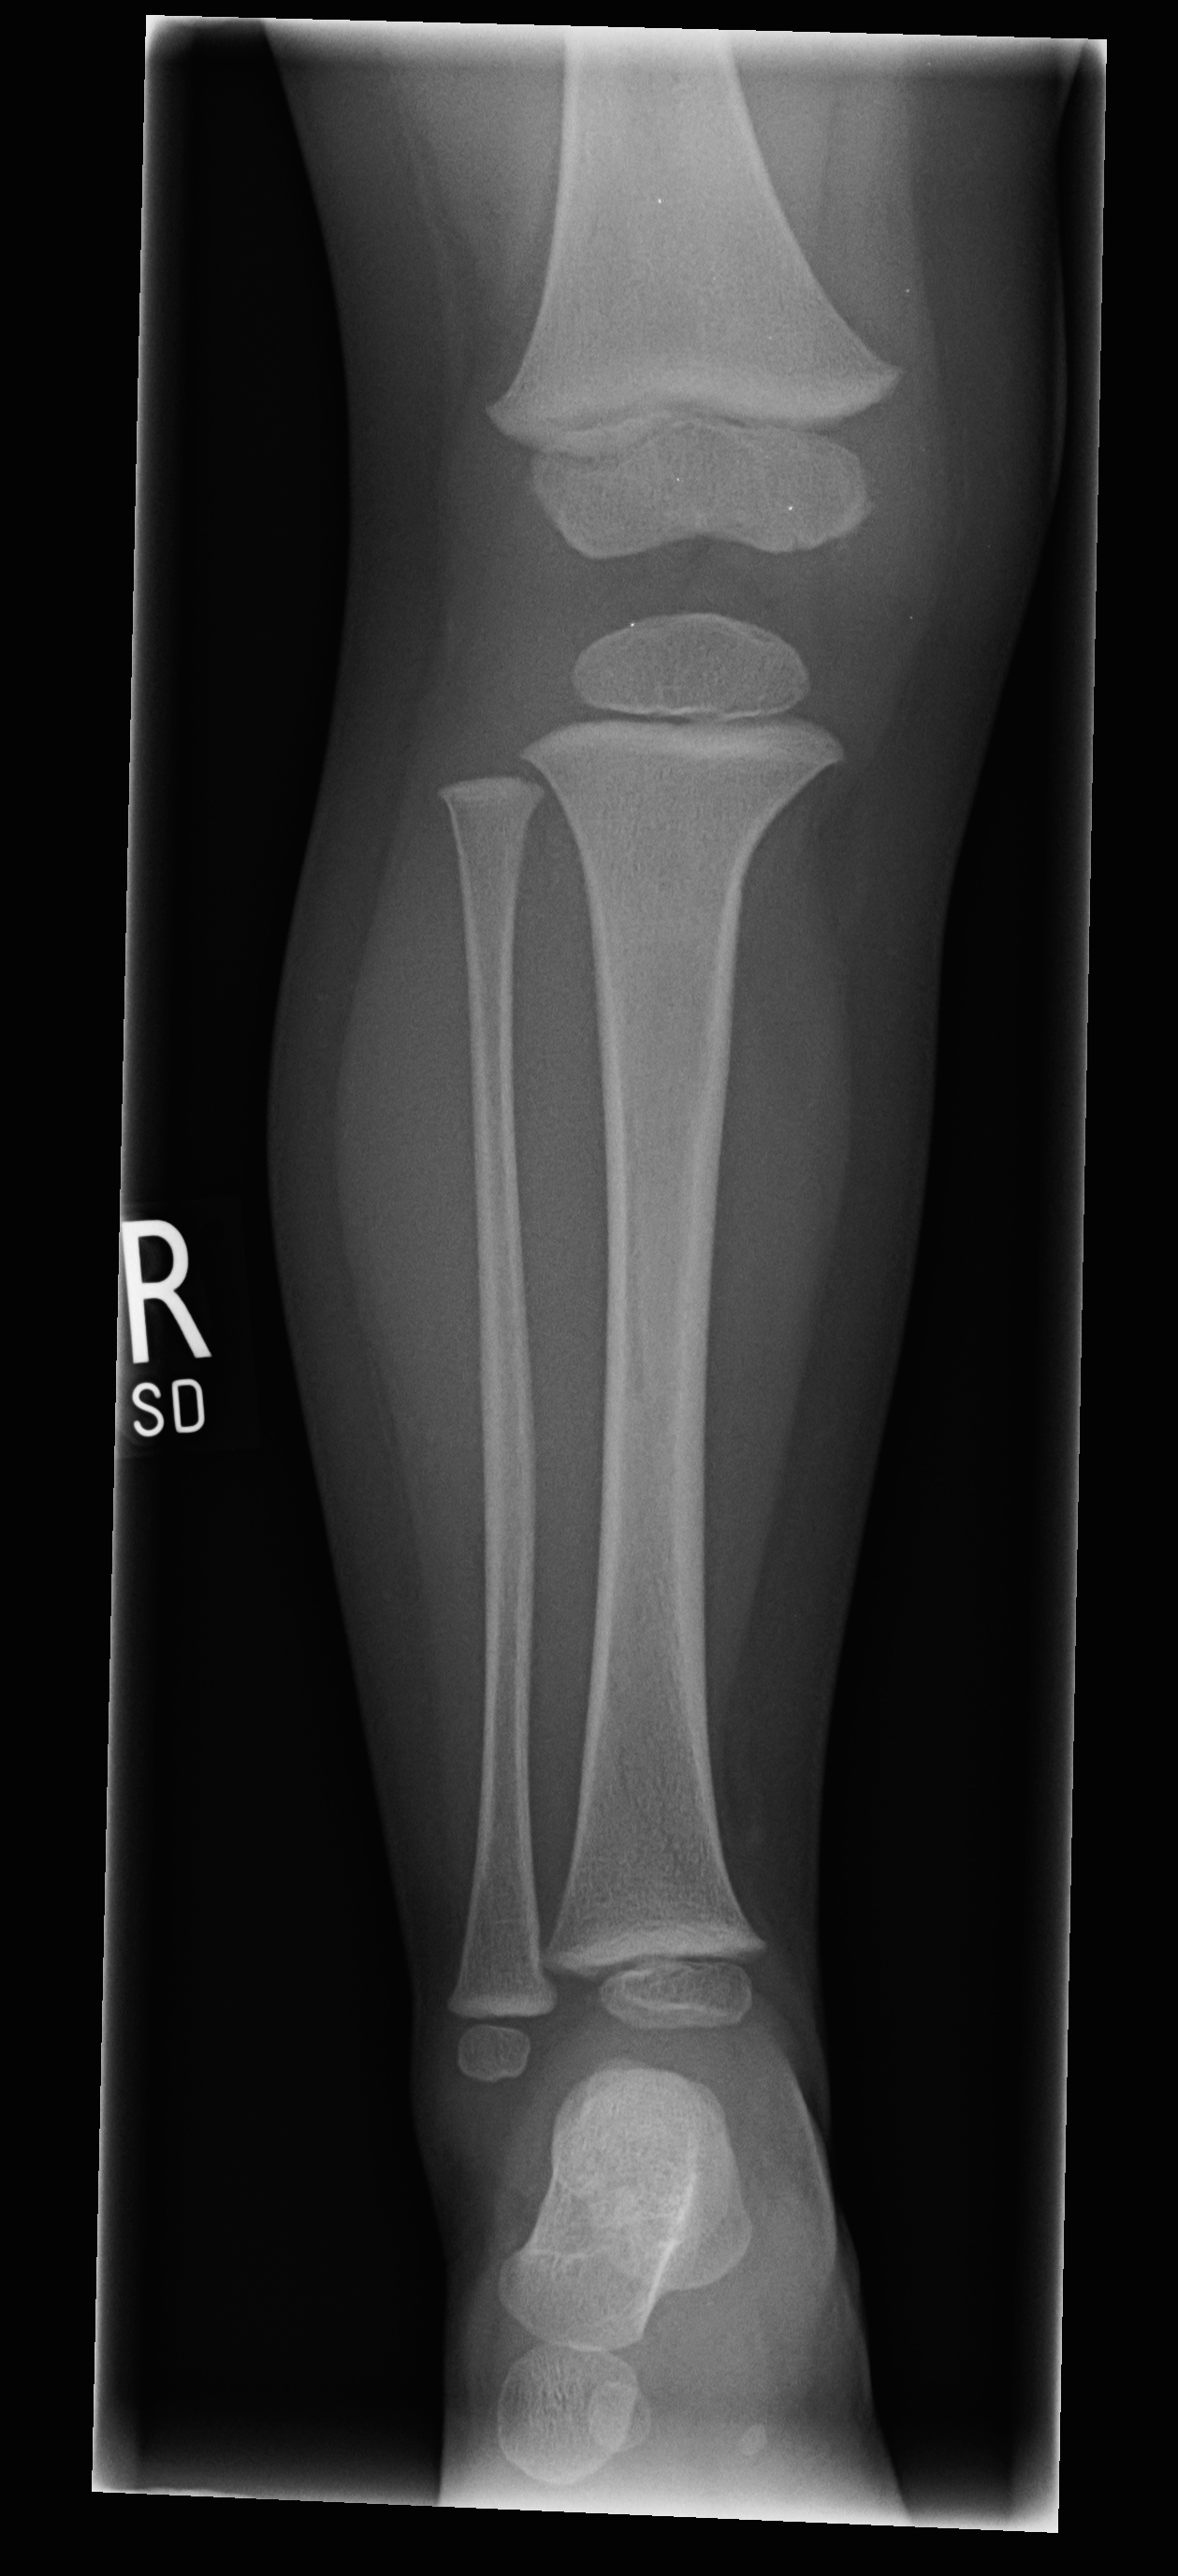

| 7 |

Abnormal fr tibia |

Abnormal Right tibial intercondylar fracture |

Correct |